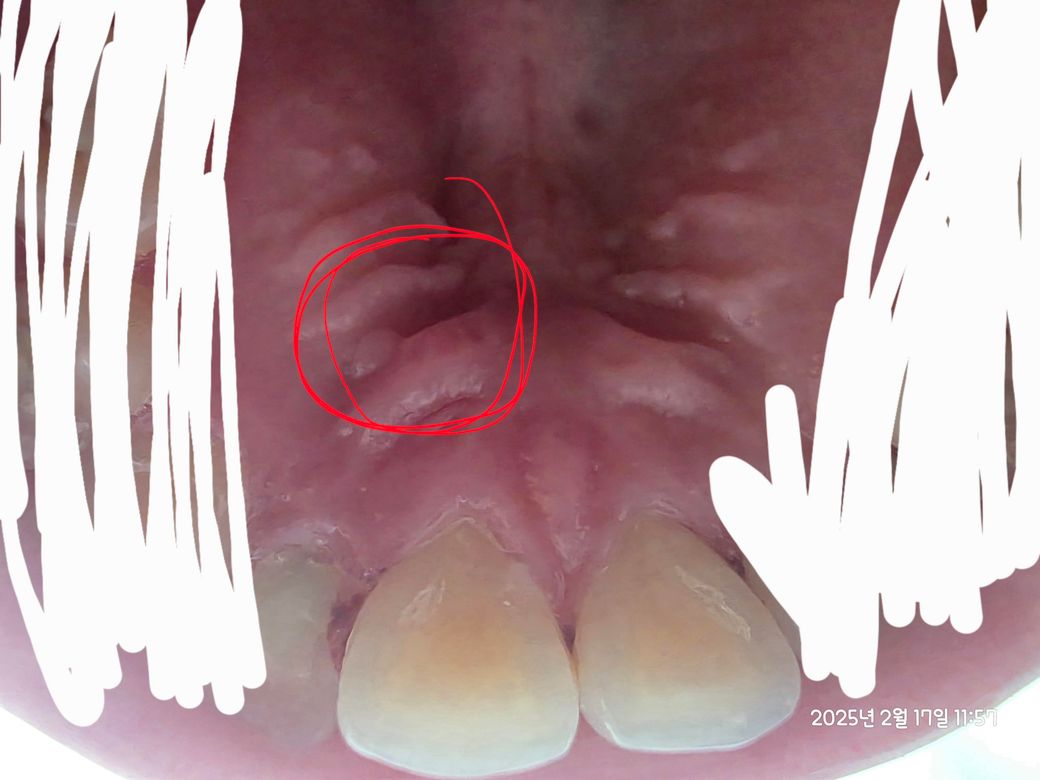

입천장에 염증 생기거나 헐었나요?ㅜㅜ

그거랑 연관된건지 아니면 별개로 헐거나 천장에도 염증이 생긴 건지 모르겠네요ㅜㅜ

사진상 제일 앞 볼록한 선? 같은 것과 두번째 사이 저 안쪽이 아파요

아 여기도 염증있는 건가요?

약간 하얀게 점같이 있는 것 같기도 한데 ㅜㅜ

염증은 아닌 것 같습니다. 치료를 받고 계신 것이라면 일단 치료받고 기다려보셔야 합니다.

상처가 좀 난 것으로 보이긴 합니다만 아직 치료도 남으셨고 치료 받으신지 얼마 안되셨으니 치료 종결될때까지 마음의 여유를 가지시길 바라겠습니다.

저부위는 염증보다는 음식등이나 뜨거운거에 자극을 받아서 그런거 같습니다. 시간이 지나면 괜찮아 지니 너무 걱정하지마세요.

사진상 봤을때 입천장 부위가 약간 염증이 있어보이긴 하네요. 잇몸치료를 한번 받으셨고, 후속 조치를 또 받으시니 이어서 치료 잘 받으시고 경과를 지켜보면 되겠습니다. 미노클린 이용하여 항생제 처치도 추가적으로 하면 좋을 것 같습니다.